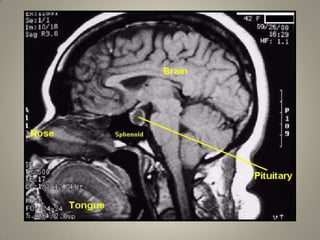

AnatomyLocationLies at the base of brain in Sella turcica.Connected with the Hypothalamus by the pituitary stalk or hypophyseal stalk.

AnatomyLocationLies at thebase of brain in Sella turcica.Connected with the Hypothalamus by the pituitary stalk or hypophyseal stalk.